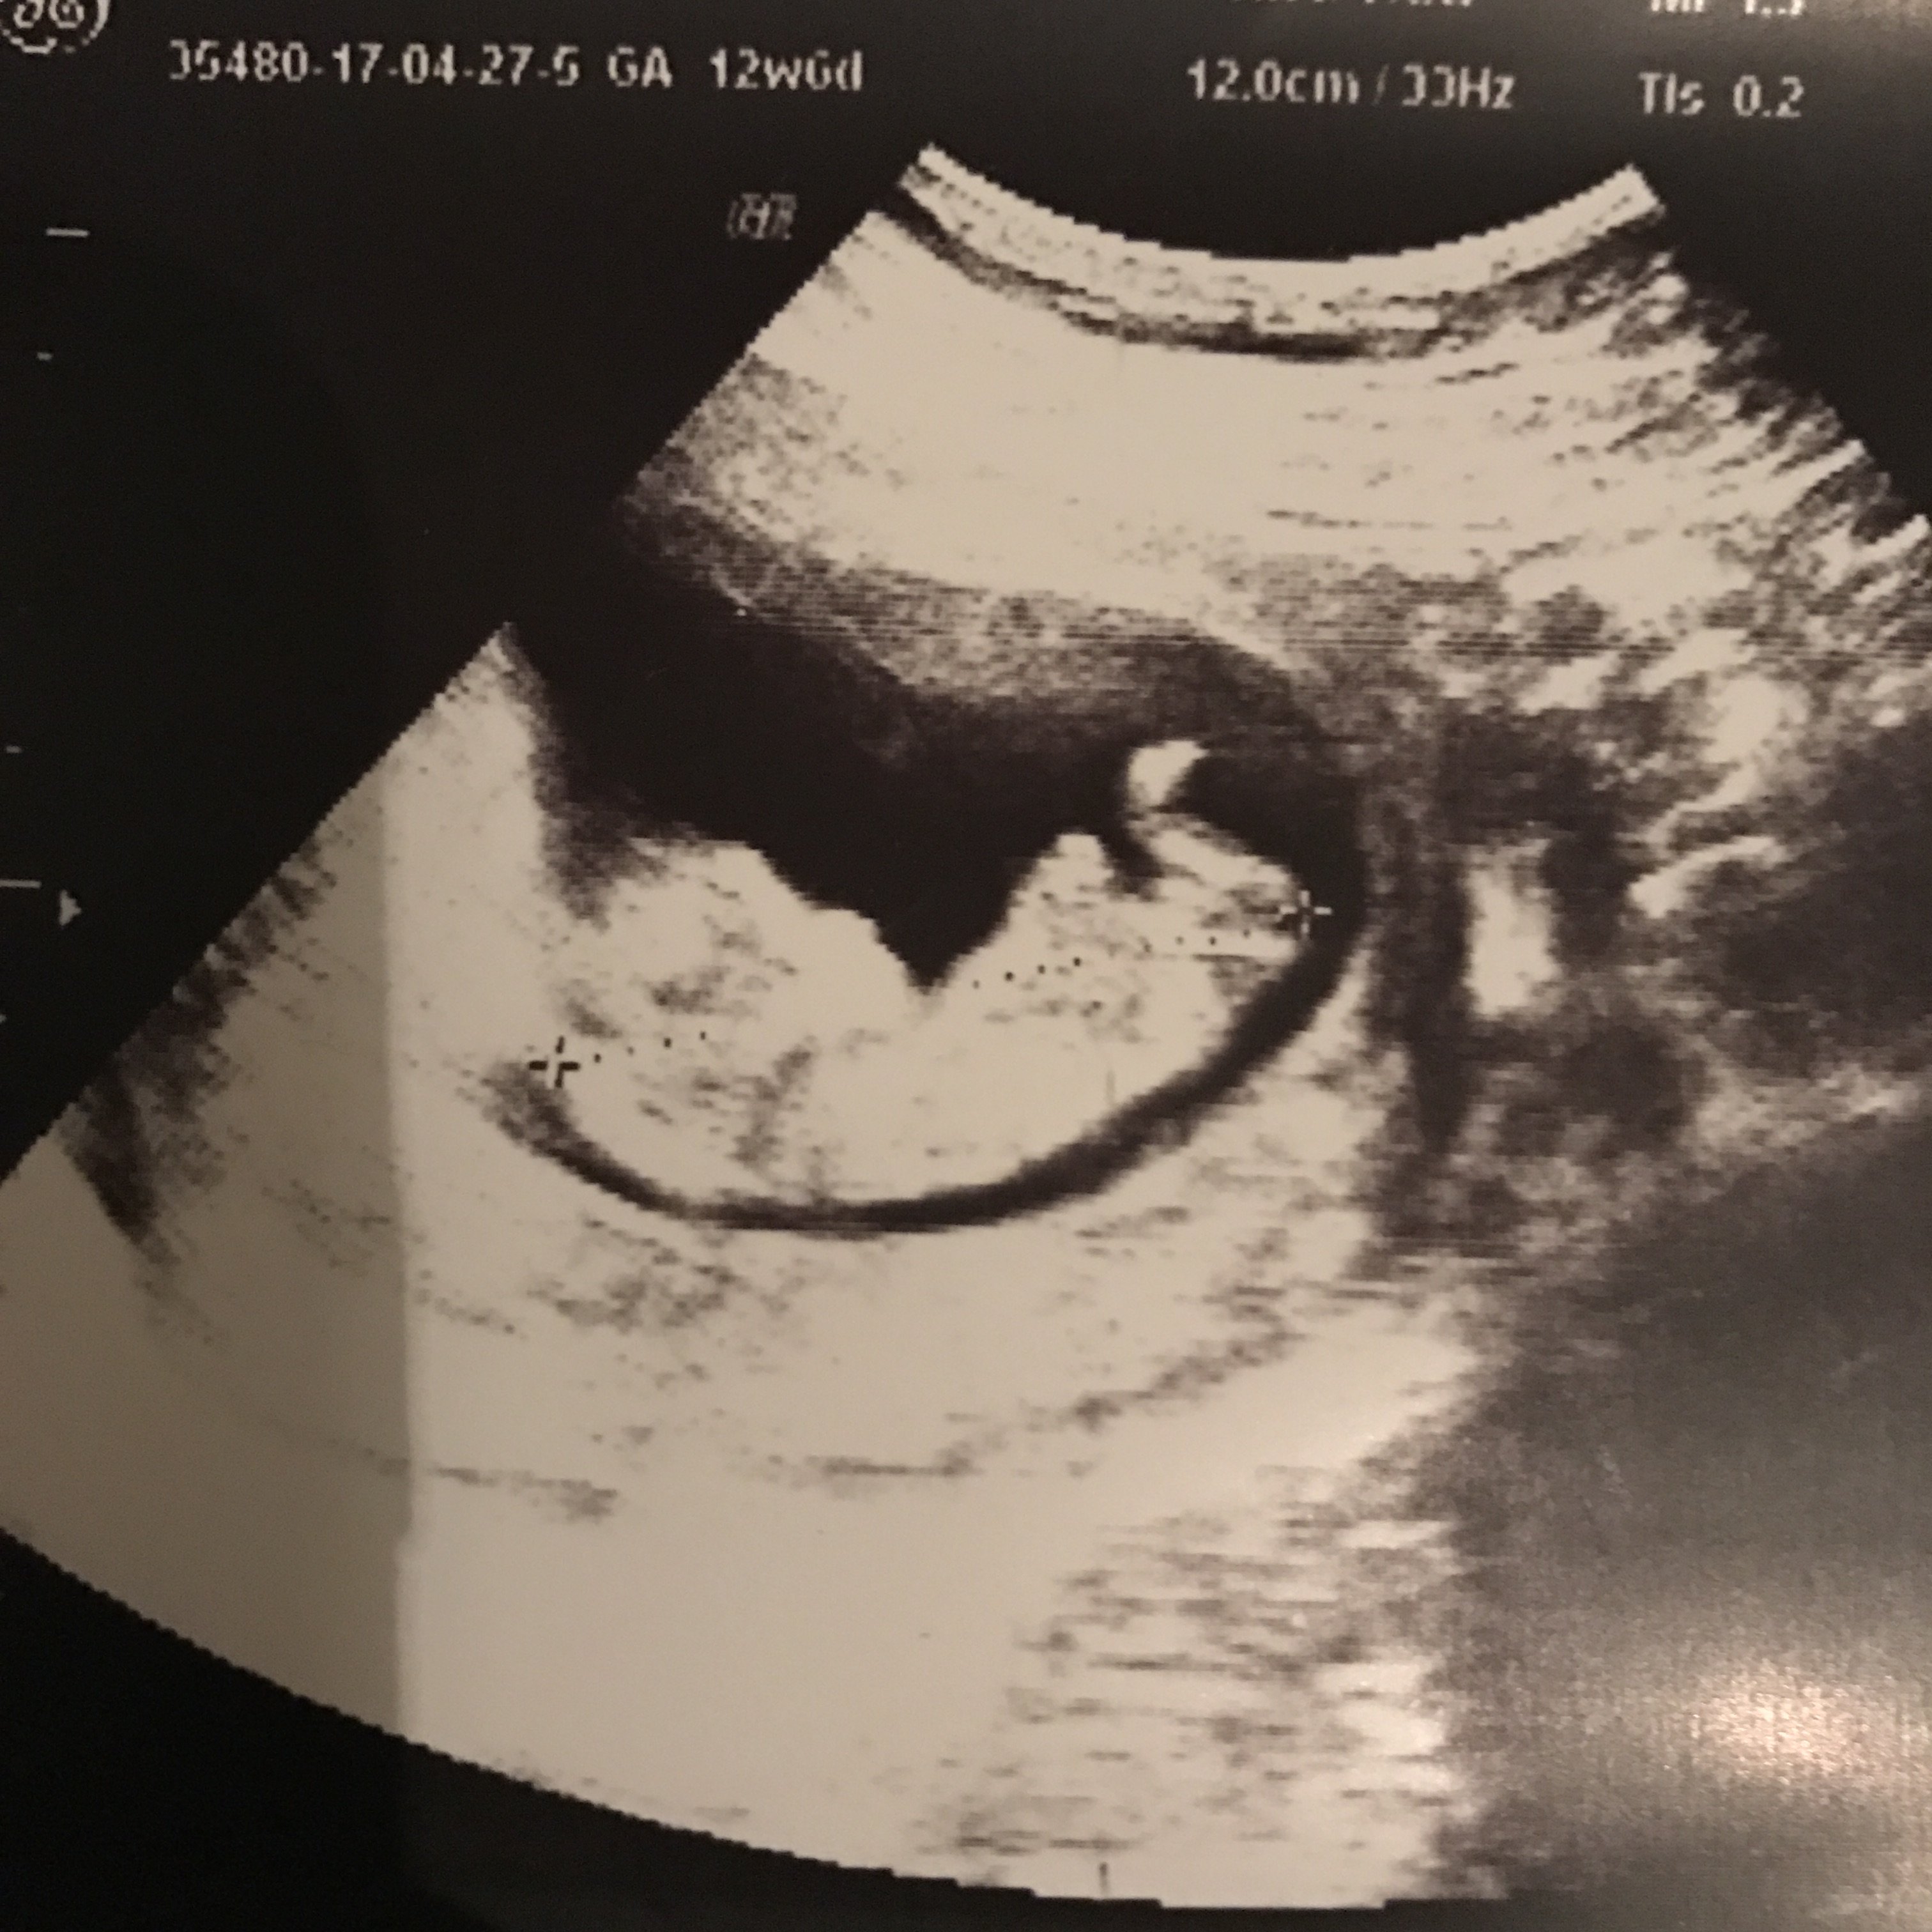

B Buglem2011 Yeni Üye Üye 26 Mayıs 2017 #285 Ekli dosyayı görüntüle 76905 Ekli dosyayı görüntüle 76906 sonunda yükledim banada yorum yaparmısınız tşkler şimdiden

Ekli dosyayı görüntüle 76905 Ekli dosyayı görüntüle 76906 sonunda yükledim banada yorum yaparmısınız tşkler şimdiden

HemşireniZ Aktif Üye Üye 26 Mayıs 2017 #287 Merhaba çıkıntının üzeri işaretli emin olmamakla birlikte bebeğinizin cinsiyetini kız olarak düşünüyorum.

Merhaba çıkıntının üzeri işaretli emin olmamakla birlikte bebeğinizin cinsiyetini kız olarak düşünüyorum.